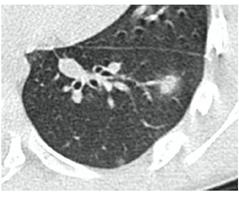

2. Наличие клинических проявлений, указанных в п. 1, в сочетании с характерными изменениями в легких по данным компьютерной томографии (КТ) (см. Приложение 1 настоящих рекомендаций) вне зависимости от результатов однократного лабораторного исследования на наличие РНК SARS-CoV-2 и эпидемиологического анамнеза.

- Изменения при КТ (рентгенографии), типичные для вирусного поражения (объем поражения минимальный или средний; КТ 1-2)

- Изменения в легких при КТ (рентгенографии), типичные для вирусного поражения (объем поражения значительный или субтотальный; КТ 3-4)

- Изменения в легких при КТ (рентгенографии), типичные для вирусного поражения критической степени (объем поражения значительный или субтотальный; КТ 4) или картина ОРДС.

КТ имеет высокую чувствительность в выявлении изменений в легких, характерных для COVID-19. Применение КТ целесообразно для первичной оценки состояния ОГК у пациентов с тяжелыми прогрессирующими формами заболевания, а также для дифференциальной диагностики выявленных изменений и оценки динамики процесса. КТ позволяет выявить характерные изменения в легких у пациентов с COVID-19 еще до появления положительных лабораторных тестов на инфекцию с помощью МАНК. В то же время, КТ выявляет изменения легких у значительного числа пациентов с бессимптомной и легкой формами заболевания, которым не требуется госпитализация. Результаты КТ в этих случаях не влияют на тактику лечения и прогноз заболевания при наличии лабораторного подтверждения COVID-19. Поэтому массовое применение КТ для скрининга асимптомных и легких форм болезни не рекомендуется.